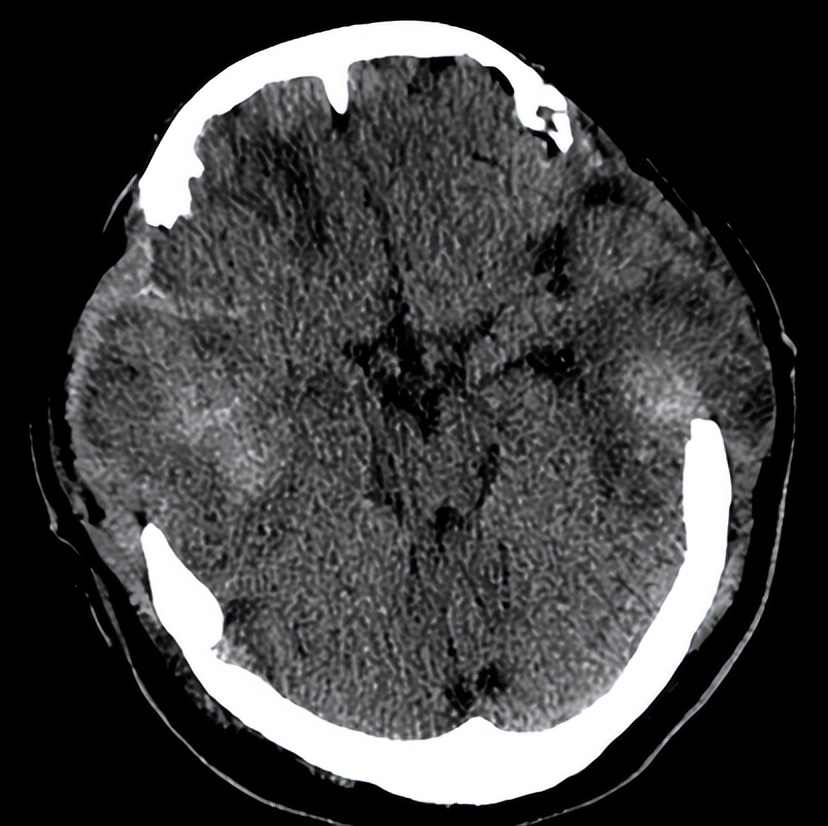

06-07 21:30术后复查头CT示: